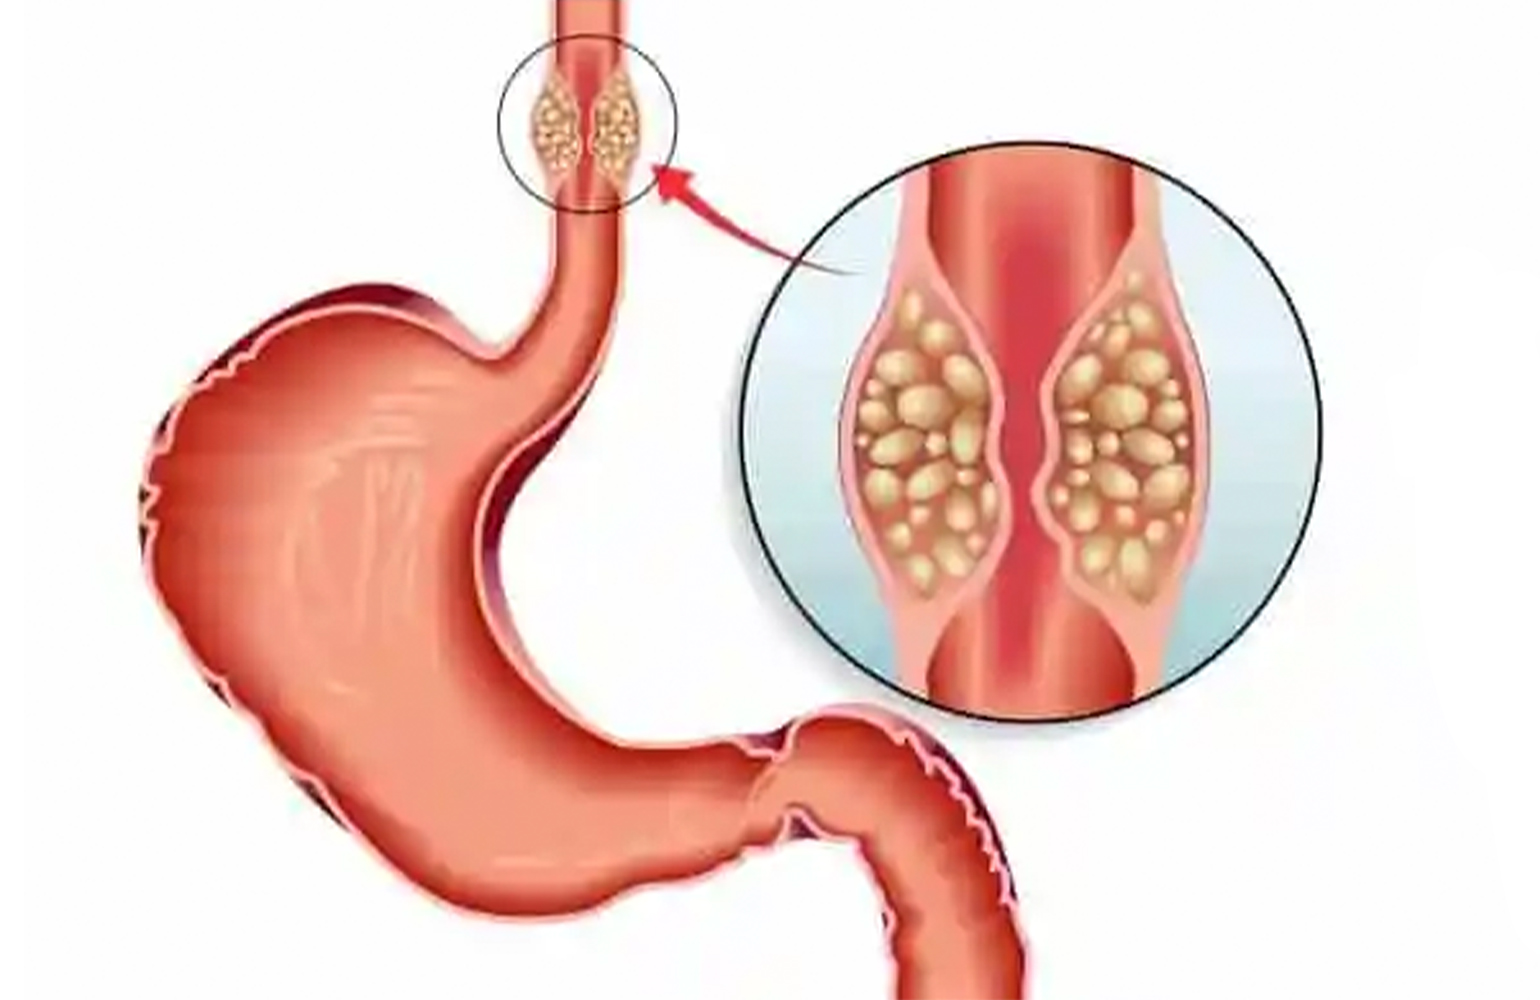

Detaylı BilgiÖzofagus (Yemek Borusu) Kanseri

Özofagus kanserinin en sık görülen semptomlarından biri yemek sırasında tıkanma hissi ve yutkunma zorluğudur.